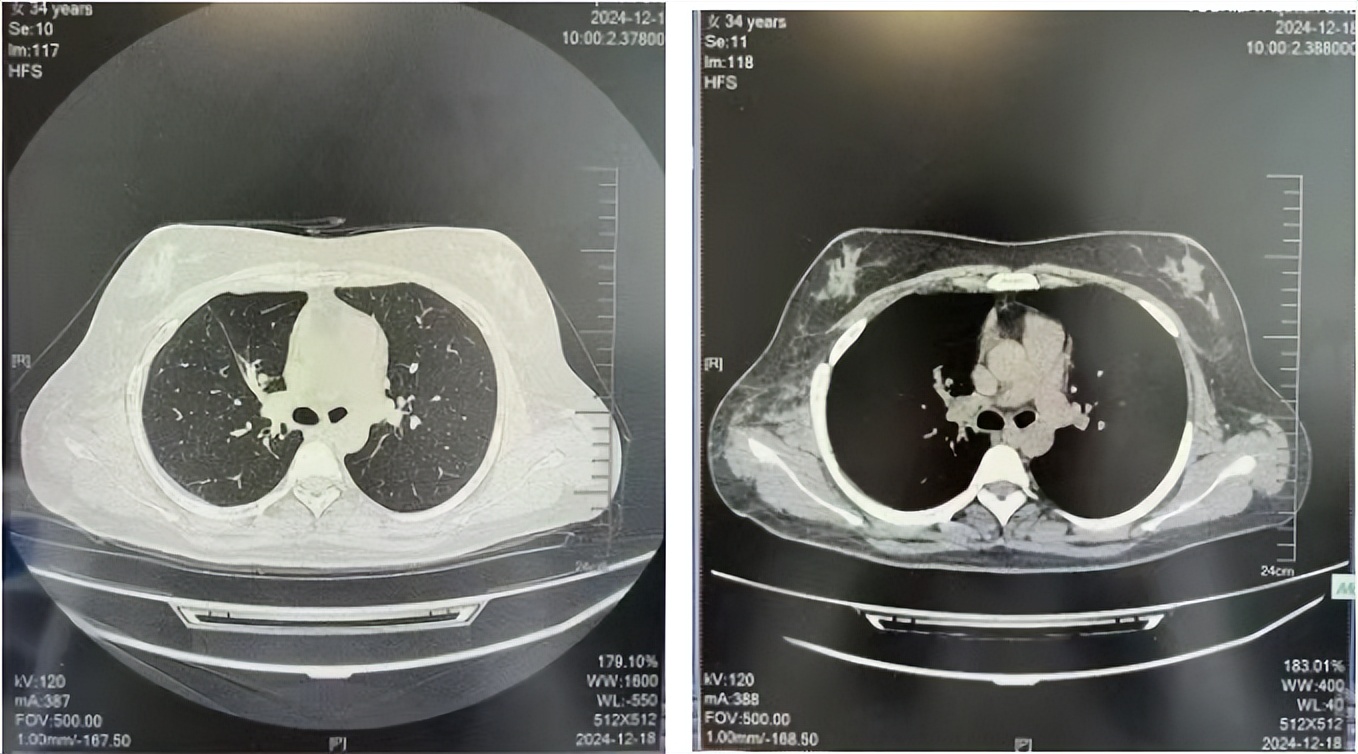

2016年1月复查CT提示支气管截断可见新发小结节,一线治疗采用培美曲塞+DDP方案化疗4周期(培美曲塞3.36,DDP 480mg)。化疗后复查胸部CT:右肺见不规则结节样影,最大层面大小约19mm*8mm,较前比较明显增大,疗效评估PD。2017.3-2017.4予单药多西他赛化疗3周期,疗效评估SD。2018年5月末复查CT提示结节较前增大,评效为PD,2018年6-10月予多西他赛+CBP化疗4周期,疗效评估SD。2022年5月患者出现活动后气短,复查胸部CT示右肺膨胀不良;右侧胸腔积液增多。胸腔积液包埋病理示符合肺腺癌细胞。行NGS基因检测:EML4:exon13-ALK:exon20融合。PD-L1(克隆号22C3)TPS<1%。

临床诊断:右肺上叶恶性肿瘤rT0N0M1a IVA期(第9版分期);恶性胸腔积液。

诊疗经过:2022年5月始口服克唑替尼3个月,出现肝功能异常(DILI 2级伴临床症状),改用恩沙替尼靶向治疗至今,目前评效为维持PR。恩沙替尼应用期间出现轻度肝功能异常(DILI 1级),对症处理后好转。截止目前PFS 33个月。

2018.07

2022.05

2022.08

2023.05

2024.12